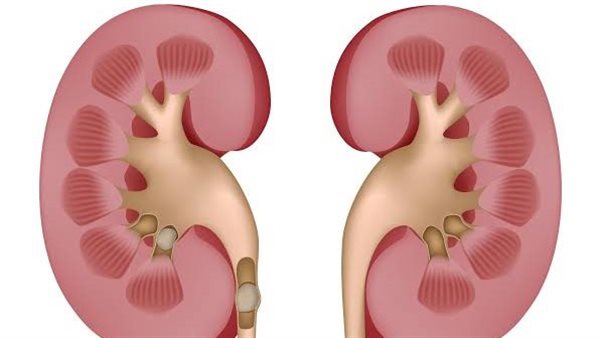

وأوضح أن الحصى عادة ما يتكون في تجويف الكلى، ولكن في حالة تصدعها تسقط داخل الحالب، مما يسبب آلاما حادة لا تحتمل.

وأشار إلى أن الحصى عادة ما يتكون من كالسيوم، وأيضا الفوسفور، بجانب الأوكسالات، وأيضا يتكون من حمض البولي، والكزونتين.

وعن أسباب حصى الكلى، أضاف أن الطبيب يشخص حصى الكلى، وفقا للبنية التجويفية للكلى ومدى تشوهها، وكذلك من حيث حجم الالتهابات التي توجد في الكلى، ونوع البكتيريا الذي يؤدي إلى مثل هذه الالتهابات، ومن ثم تؤدي إلى تكون الحصى، وليس ذلك فقط بل بعض الأمراض الوراثية، وأيضا في حالة تناول أدوية لعلاج الفيروسات.